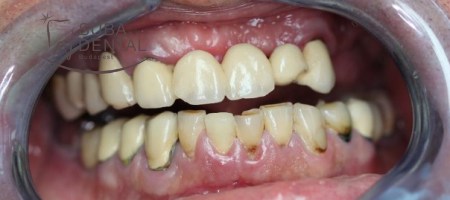

The finished fixed restoration borne by implants and natural teeth.

Before

After

Turnaround time for the permanent tooth restoration from the first encounter was 2 years.